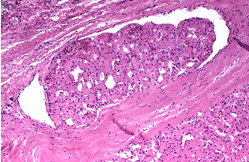

Histopathological examination of parathyroid adenocarcinoma (Courtesy Dr. V. Penopoulos)